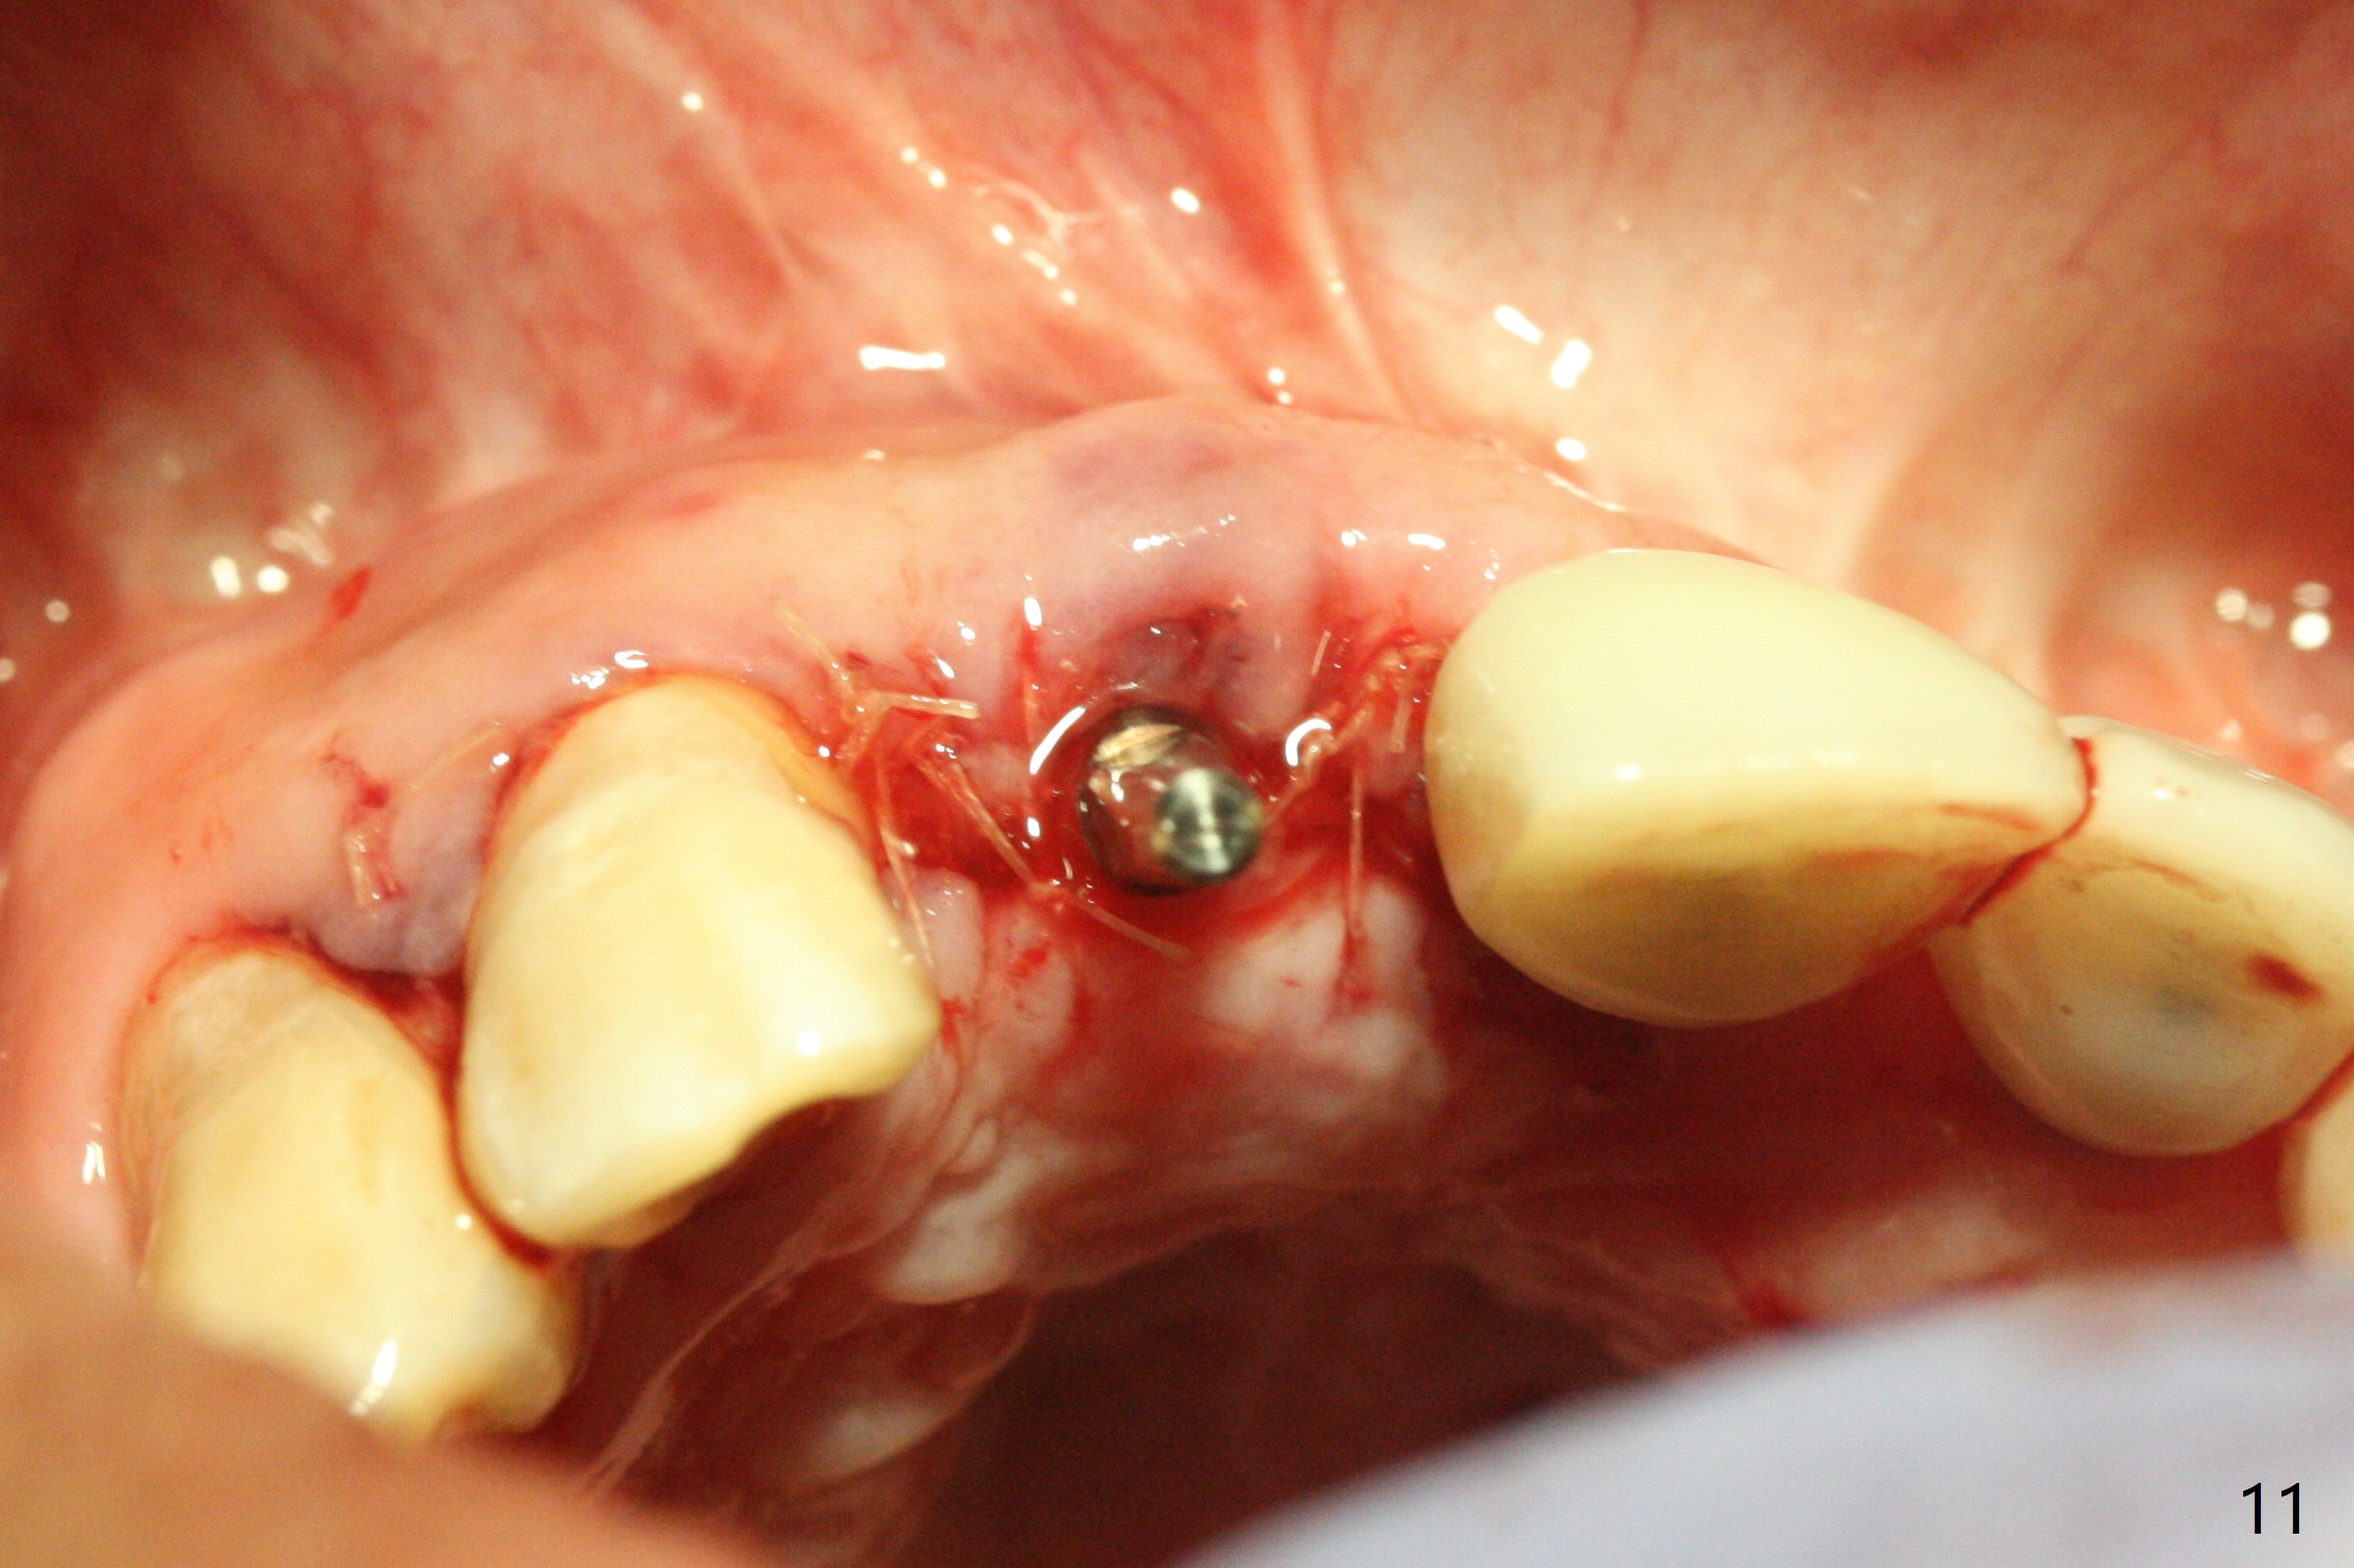

A 43-year-old man has 6 of 1-piece implants in the maxilla (#8-13). His daughter's head hits his upper anterior teeth 7 months post cementation. Exam shows that the tooth #7 has mild percussion. Nine months later the implant crown at #8 becomes displaced and loose when he bites apple (Fig.1 arrow). Forceps are used to remove the crown, leaving a concave implant site (Fig.2). After the crown is bonded to the neighboring tooth/implant crown (Fig.3 *), the patient feels pain from the neighboring tooth. The alveolus is 4.3 mm wide (Fig.4 (2.9 mm preop)), allowing 2.5 or 3.0 mm immediate implant re-placement (Fig.5). A 2.0/3.0 mm trephine bur will be used for implant removal. Try to place the new implant slightly distal to improve the trajectory (Fig.6). Particulate and/or onlay graft is an option. Prepare dummy implants. As planned, the fractured implant is removed by using a 2.0/3.0 mm trephine bur following incision (Fig.7). After use of Lindamann bur to remove the distal bone, a 3x14(4) mm dummy implant is placed with 20 Ncm (Fig.8). A longer implant could be used (3x16(2 or 4) mm), but a 3.5x13 mm 1-piece implant is placed with ~ 50 Ncm after use 3.0 mm drill (Fig.9,10). Allograft is placed around the implant (Fig.9,10 *), followed by Amnion-Chorion membrane and 5-0 PGA sutures (Fig.11). Allograft placed around the implant (Fig.9 *) appears to be able to prevent implant thread exposure 4 months postop (Fig.12). PA is taken when the crown is cemented (Fig.13). Four months postop cementation of #8 crown, the patient returns because of #9 mobility (Fig.14). In fact the implant fractures when the loose crown is removed with forceps; there is bone loss at #10. Bone graft will be placed at #10 with sticky bone (PRFx1), while the implant at #9 is redo. The ridge is wide enough for a 3.5x10 mm implant (Fig.16 (CT taken when #8 implant fractured)). Also prepare Tatum angled 1-piece implant. The 2 mm implant is too thin when occlusion contact at #10-13 is incomplete. The crowns will be redone when the implant at #9 is osteointegrated.